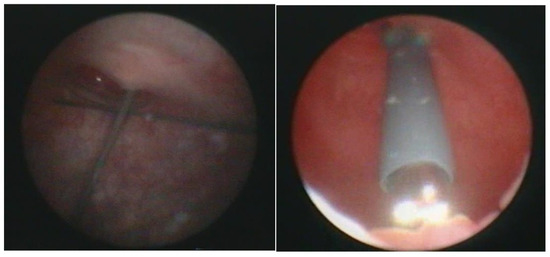

Figure 2.

Combined antegrade and retrograde endoscopy.

Figure 3.

Transurethral cystoscopy controlling the percutaneous suprapubic bladder access.